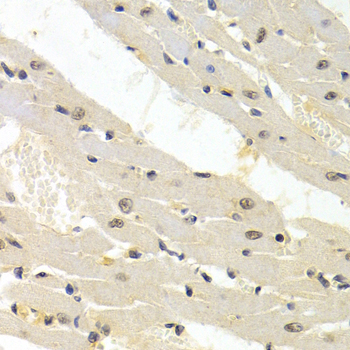

Immunohistochemistry of paraffin-embedded rat heart using TRIM63 antibody at dilution of 1:200 (400x lens).